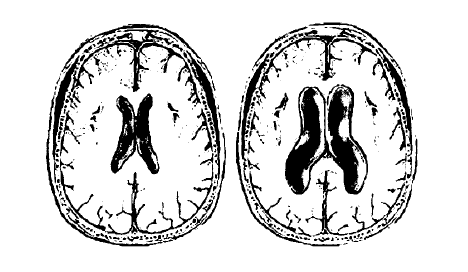

В некоторых случаях эти патологические процессы приводят к повышению внутричерепного давления, расширению желудочков мозга и подоболочечных пространств (гидроцефалии).